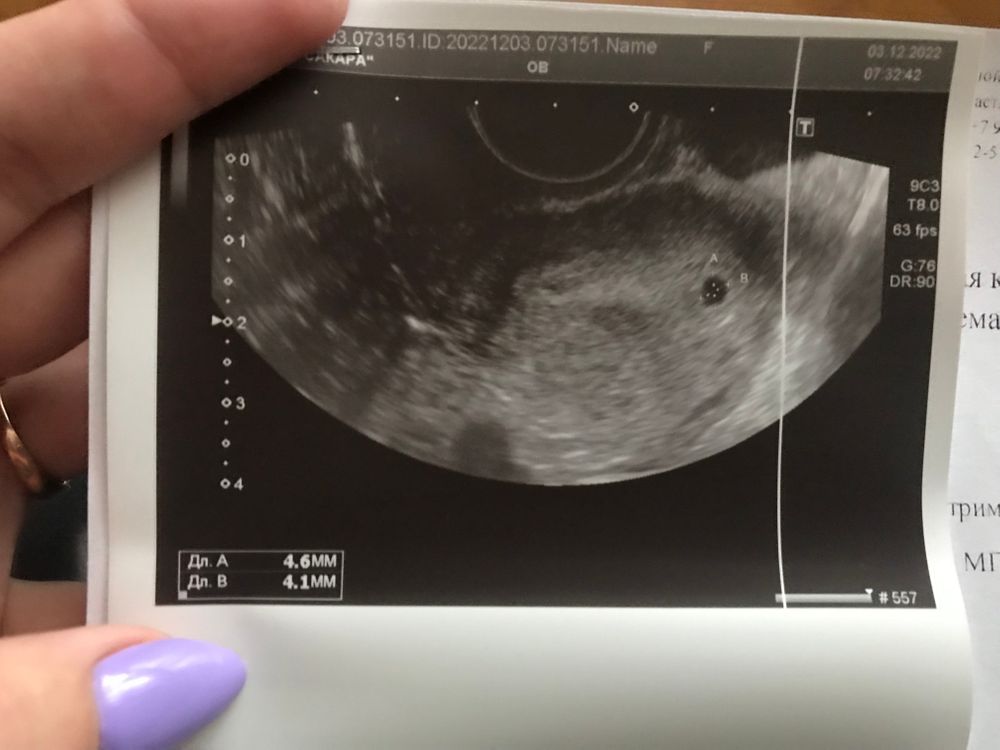

Ирина, надеюсь на хорошее узи🙏 в субботу утром делала, пя было 4,7 на 4,1 по идее должно подрости чутка?

Екатерина, маточная. Делала узи как раз перед тем, как начала идти кровь. Изображение Изображение